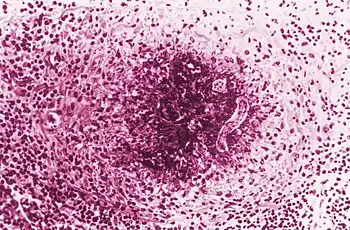

Finding Toxocara larvae within a patient is the only definitive diagnosis for toxocariasis; however, biopsies to look for second stage larvae in humans are generally not very effective.[9] PCR, ELISA, and serological testing are more commonly used to diagnose Toxocara infection.[9] Serological tests are dependent on the number of larvae within the patient, and are unfortunately not very specific.[9] ELISAs are much more reliable and currently have a 78% sensitivity and a 90% specificity.[26] A 2007 study announced an ELISA specific to Toxocara canis, which will minimize false positives from cross reactions with similar roundworms and will help distinguish if a patient is infected with T. canis or T. cati.[27] OLM is often diagnosed after a clinical examination.[26] Granulomas can be found throughout the body and can be visualized using ultrasound, MRI, and CT technologies.[9]